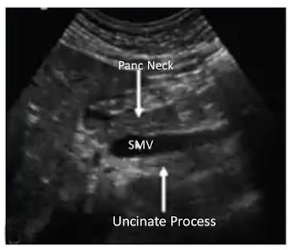

Label the Sagittal Image

Black = ?

Blue = ?

Red = ?

Black = Pancreatic Neck

Blue = SMV

Red = Uncinate Process